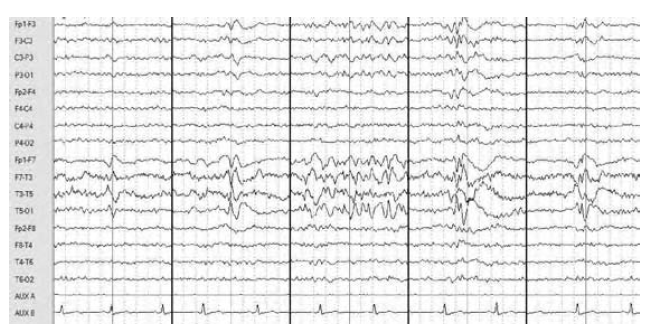

WHAT ED ARE SEEN?

Different morphologies include sharp waves (seen during seconds 1 and 2), spikes and sharp waves (in second 3), polyspike-and-slow waves (in second 4), and spike-and-wave discharges (in the last second of the figure) recorded during an ambulatory EEG in a patient with epilepsy.